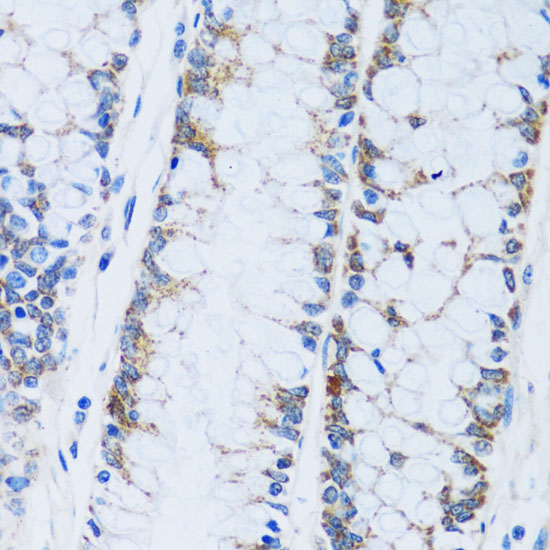

Immunohistochemistry of paraffin-embedded human colon using CA13 at dilution of 1:100 (40x lens).

Immunohistochemistry of paraffin-embedded human breast cancer using CA13 at dilution of 1:100 (40x lens).

Immunohistochemistry of paraffin-embedded mouse kidney using CA13 at dilution of 1:100 (40x lens).